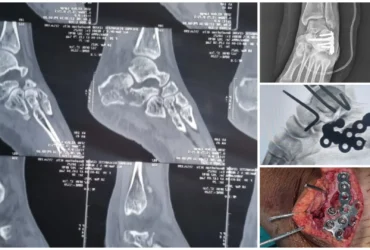

●DEFORMITY CORRECTION

●COMPLICATED FRACTURES

●FAILED FRACTURES

●TRAUMA CARE WITH DEEP ACCURANCY

We Provide Orthopedic Service by Experience Doctors

We has a dedicated multidisciplinary team that cares for and surgically repairs acute fractures for patients of all ages. We offer expertise in fractures of the hip, arm, leg, hand, foot and ankle.

Masquelet Technique & Ilizarov for Distal Tibia Bone Defect | Balanku Hospital